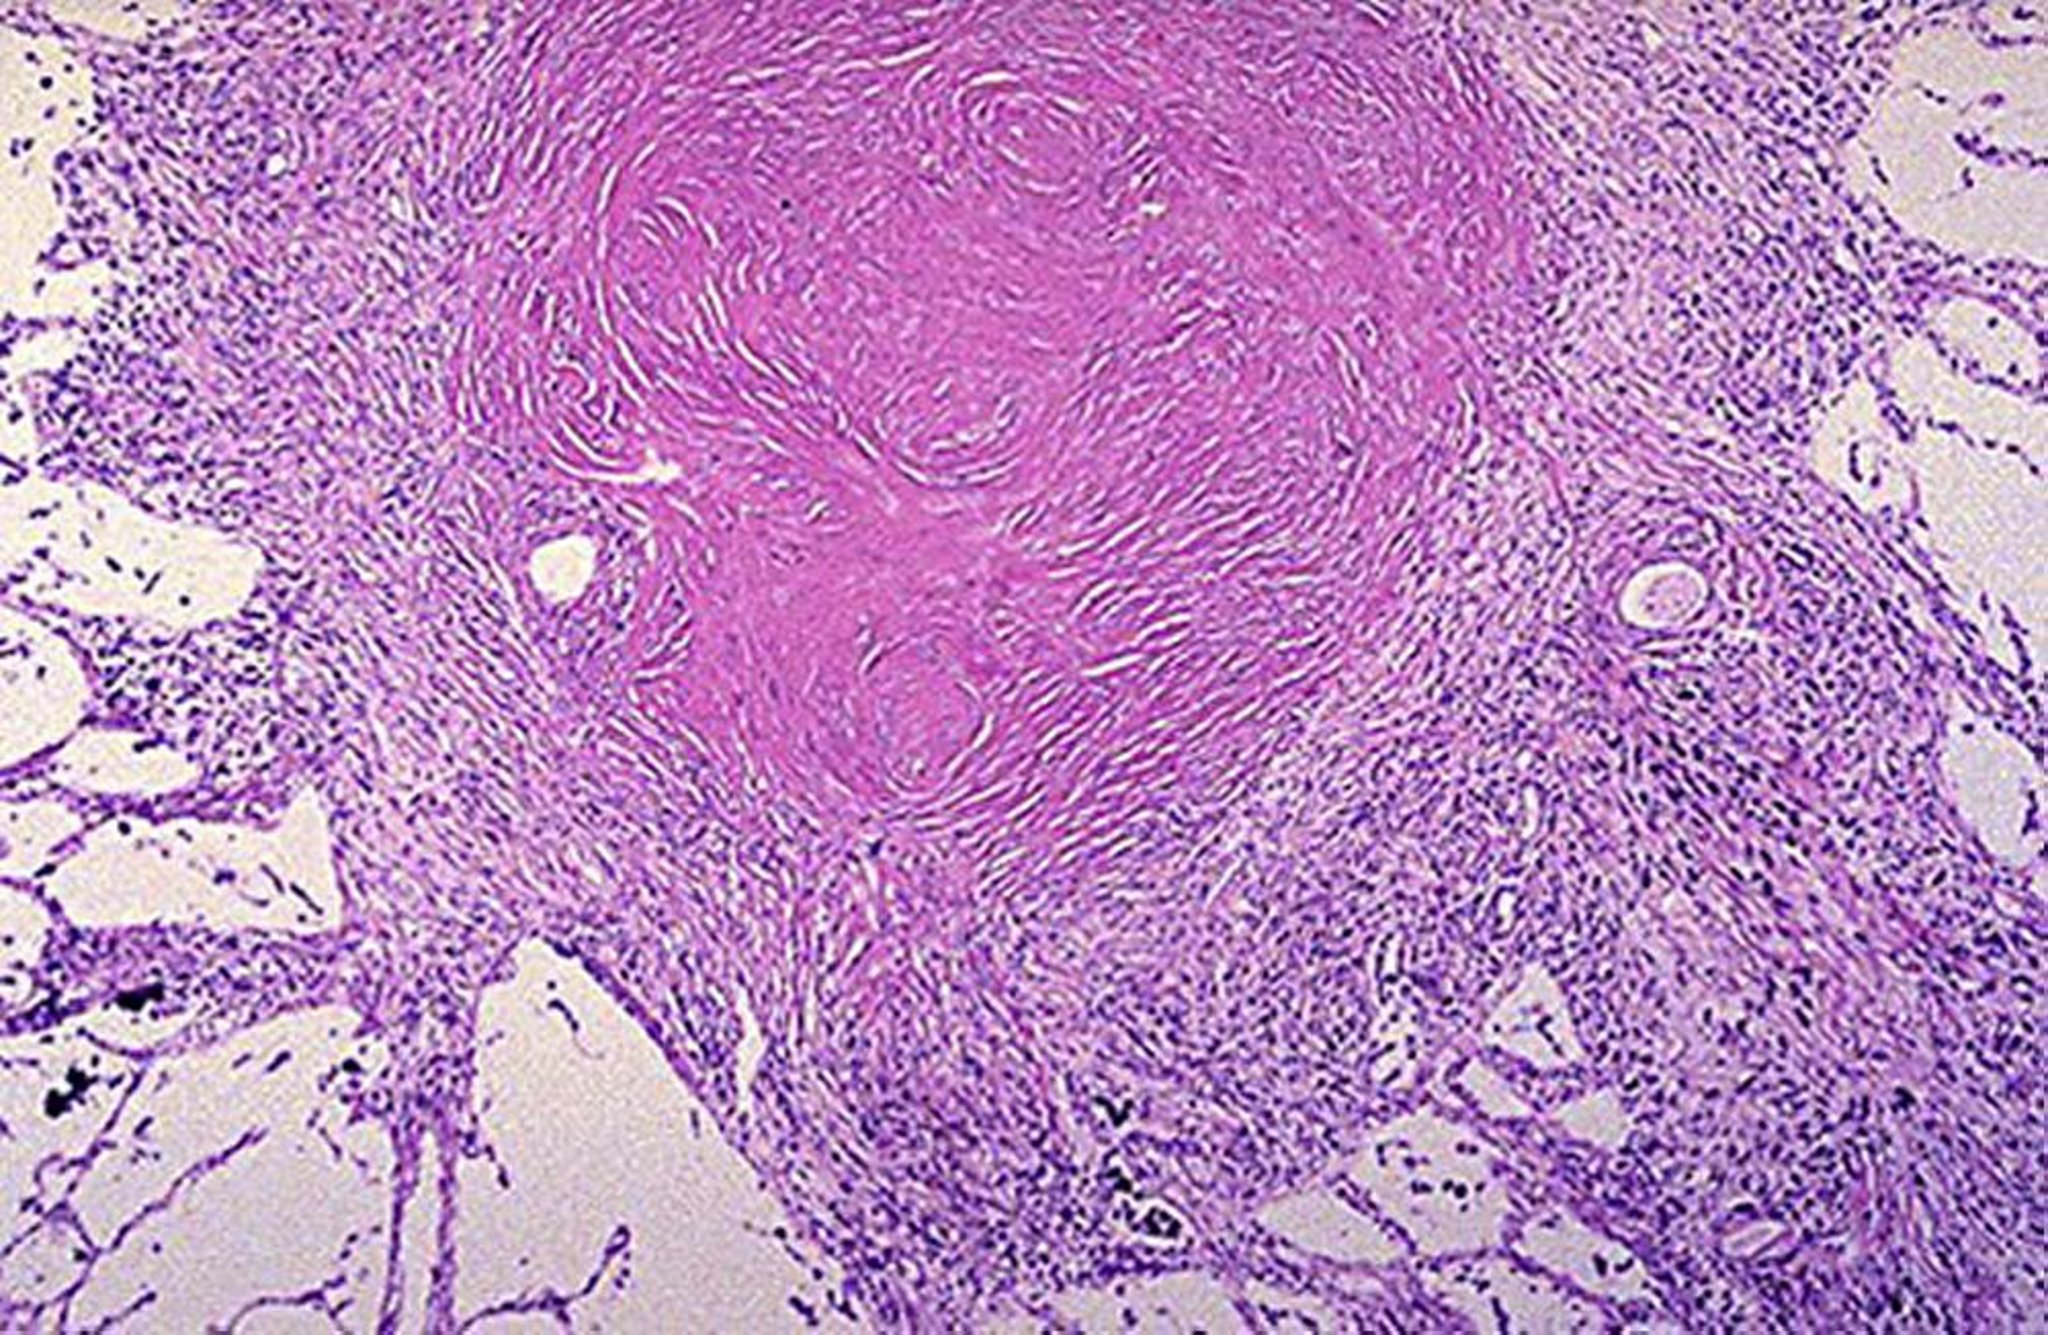

Nodule silicotique

Image courtoisie de David W. Cugell, MD.